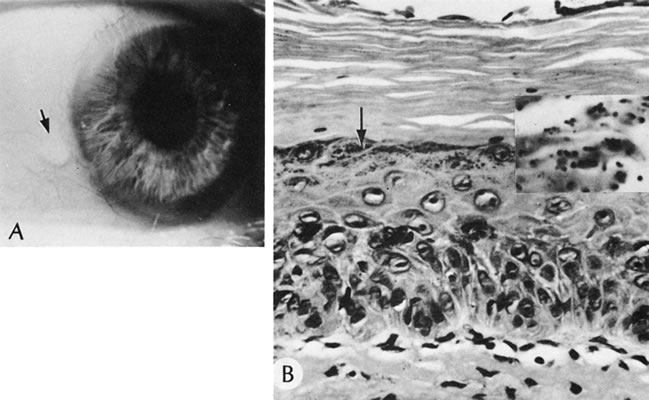

EPIDEMIC KERATOCONJUNCTIVITIS

Epidemic keratoconjunctivitis (EKC) is a highly contagious, self-limited subepithelial inflammatory disease associated most often with adenovirus type 8 and less commonly with adenovirus types 19 and 25.92 The disease often occurs as epidemics in factories, schools, or offices of ophthalmologists. The viral particles remain infectious for up to 14 days on metal, glass, or plastic surfaces (e.g., tonometer heads). An incubation period of approximately 8 days occurs between infection and clinical expression in the first eye followed 3 to 7 days later by expression in the second eye. The second eye usually is involved less severely. The onset often is abrupt or explosive, consisting of follicular conjunctivitis associated with tearing, marked swelling and hyperemia of the conjunctiva, and ipsilateral, painful preauricular lymphadenopathy (Fig. 10). In children, EKC can mimic the presentation of orbital cellulitis.93 Conjunctival membranes may develop during the course of EKC, which in turn may lead to filamentary keratitis and/or frank symblepharon formation. Subepithelial keratitis occurs during the second or third week, often reducing visual acuity significantly (20/60).94

Fig. 10. Inflammatory membrane associated with epidemic keratoconjunctivitis (EKC) caused by adenovirus type 8. The entire inferior tarsal conjunctive is covered by thick, tenaceous, fibrinous exudate.

Historically, very few tissue specimens have been studied. Initially, lymphocytes infiltrate the subepithelial area of the cornea, followed by mild scarring. The resulting nebula may be permanent.